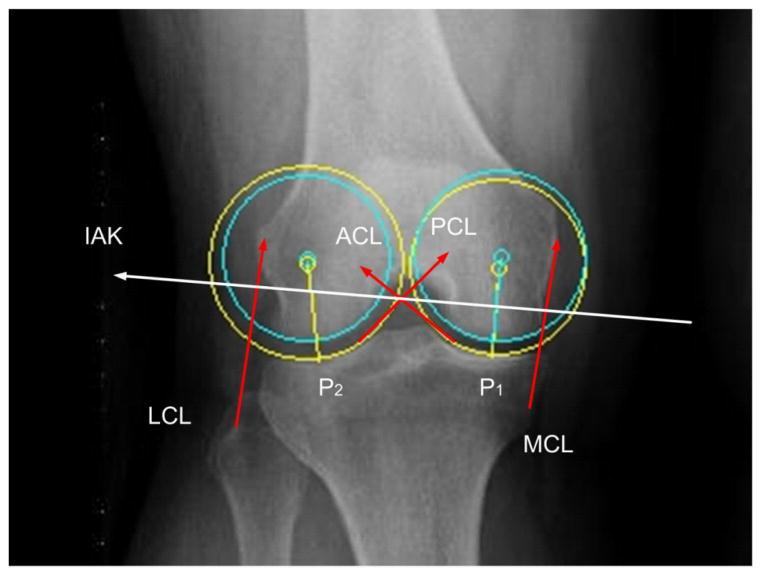

An Informational Algorithm as the Basis for Perception-Action Control of the Instantaneous Axes of the Knee.

Traditional locomotion studies emphasize an optimization of the desired movement trajectories while ignoring sensory feedback. We propose an information based theory that locomotion is neither triggered nor commanded but controlled. The basis for this control is the information derived from perceiving oneself in the world. Control therefore lies in the human-environment system. In order to test this hypothesis, we derived a mathematical foundation characterizing the energy that is required to perform a rotational twist, with small amplitude, of the instantaneous axes of the knee (IAK). We have found that the joint's perception of the ground reaction force may be replaced by the co-perception of muscle activation with appropriate intensities. This approach generated an accurate comparison with known joint forces and appears appropriate in so far as predicting the effect on the knee when it is free to twist about the IAK.